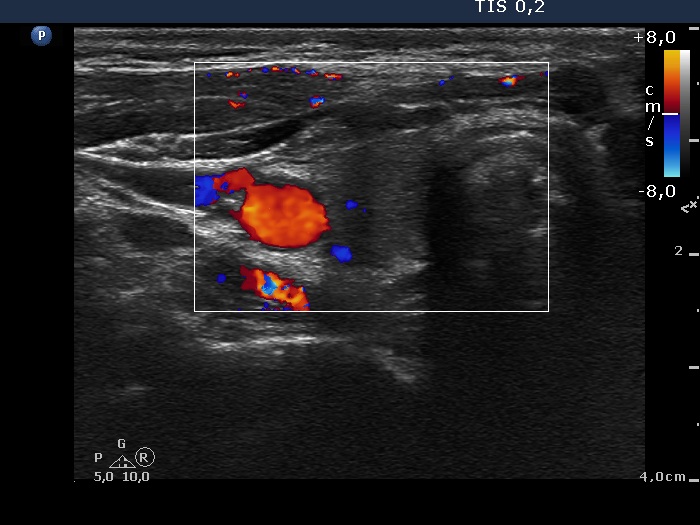

The operated thyroid - Case 7. A patients after a bilateral subtotal resection

Right lobe, horizontal scan, color Doppler method. The vascularization is not specific.